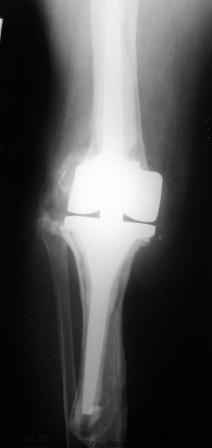

Уважаемые коллеги!Хотелось бы услышать Ваше мнение о возможности и способе помощи больной. 1939 г.р. В 1995г. эндопротезирование правого коленного сустава протезом Феникс, в 1999г. в г. Томске - ревизия - ротационный хинч W.Link. C 2005г. прогрессирует варусная деформация за счетнестабильности тибиального компонента. Попытка ортезирования - без эффекта. Попытка направить в ФСМУ без эффекта, да и больная не хочет никуда ехать.С уважением, Leonid

Технически можно надеть гвоздь на ножку протеза

Понятно что для решения на операцию артродеза необходимы веские причины. Но я не уверен что здесь асептическое расшатывание. Судя по снимкам, бедренный компонент стоит не плохо, и есть рассасывание костной ткани вокруг всего протеза в голени. Что-то мне подсказывает об инфекционном процессе, возможно вялотекущем. В наших условиях я сделал бы обследование включающее анализы крови с СОЭ, СРБ. Сделал бы пункцию коленного сустава или даже биопсию мягких тканей для посева и микроскопии.